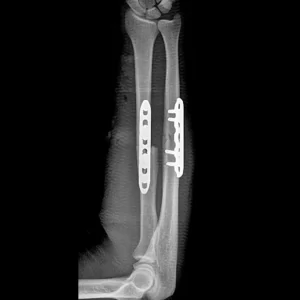

Placa INNOBLOX

Sistema 3.5

Bloqueada

Indicaciones

Fracturas Diafisiarias Radio y Cúbito